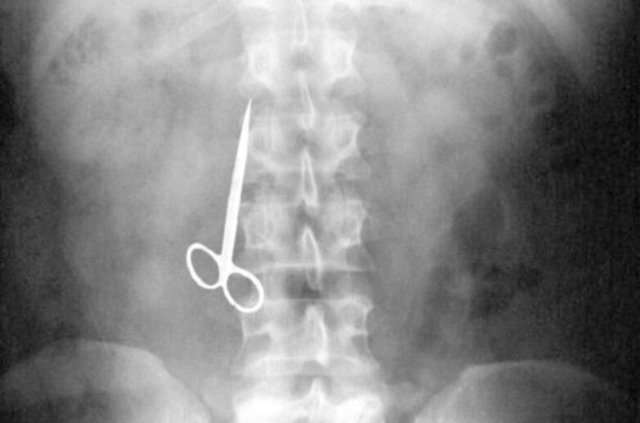

Genellikle yabancı cisimler 'X' ışınıyla görülebilir. Direk grafi ile metal ve 'X' ışınına duyarlı cisimleri rahatlıkla görebiliyoruz. Ama plastikleri göremiyoruz. Bu durumda oyuncağın bir parçasıyla yutulan parçayı anlamaya çalışıyoruz."

Hastaneye yabancı cisim yutma şikayetiyle getirilen çocuğun ilk etapta takip edildiğini, yaşına ve yuttuğu objenin özelliğine göre de müdahaleye karar verildiğini belirten Dr. Miray Karakoyun, yabancı cisim yutma şikayetiyle başvuran hastalarda, yabancı cismin ne olduğu, çocuğun kaç yaşında olduğu ve yutulan maddenin çekilen filmi sonucu sistemin neresinde olduğunun kendileri için önemli olduğunu kaydederek şöyle dedi:

"Madeni paralar çok sık yutulan cisimler arasında, 4-6 haftaya kadar midede ya da bağırsaktaysa bekleyebiliyoruz ancak yemek borusunda olan vakalarda yutulan yabancı cisim ne olursa olsun endoskopi işlemi yapıyoruz. İkili mıknatıs yutmalarına hemen müdahale ediyoruz. Yoksa ciddi zararlara yol açabiliyor.